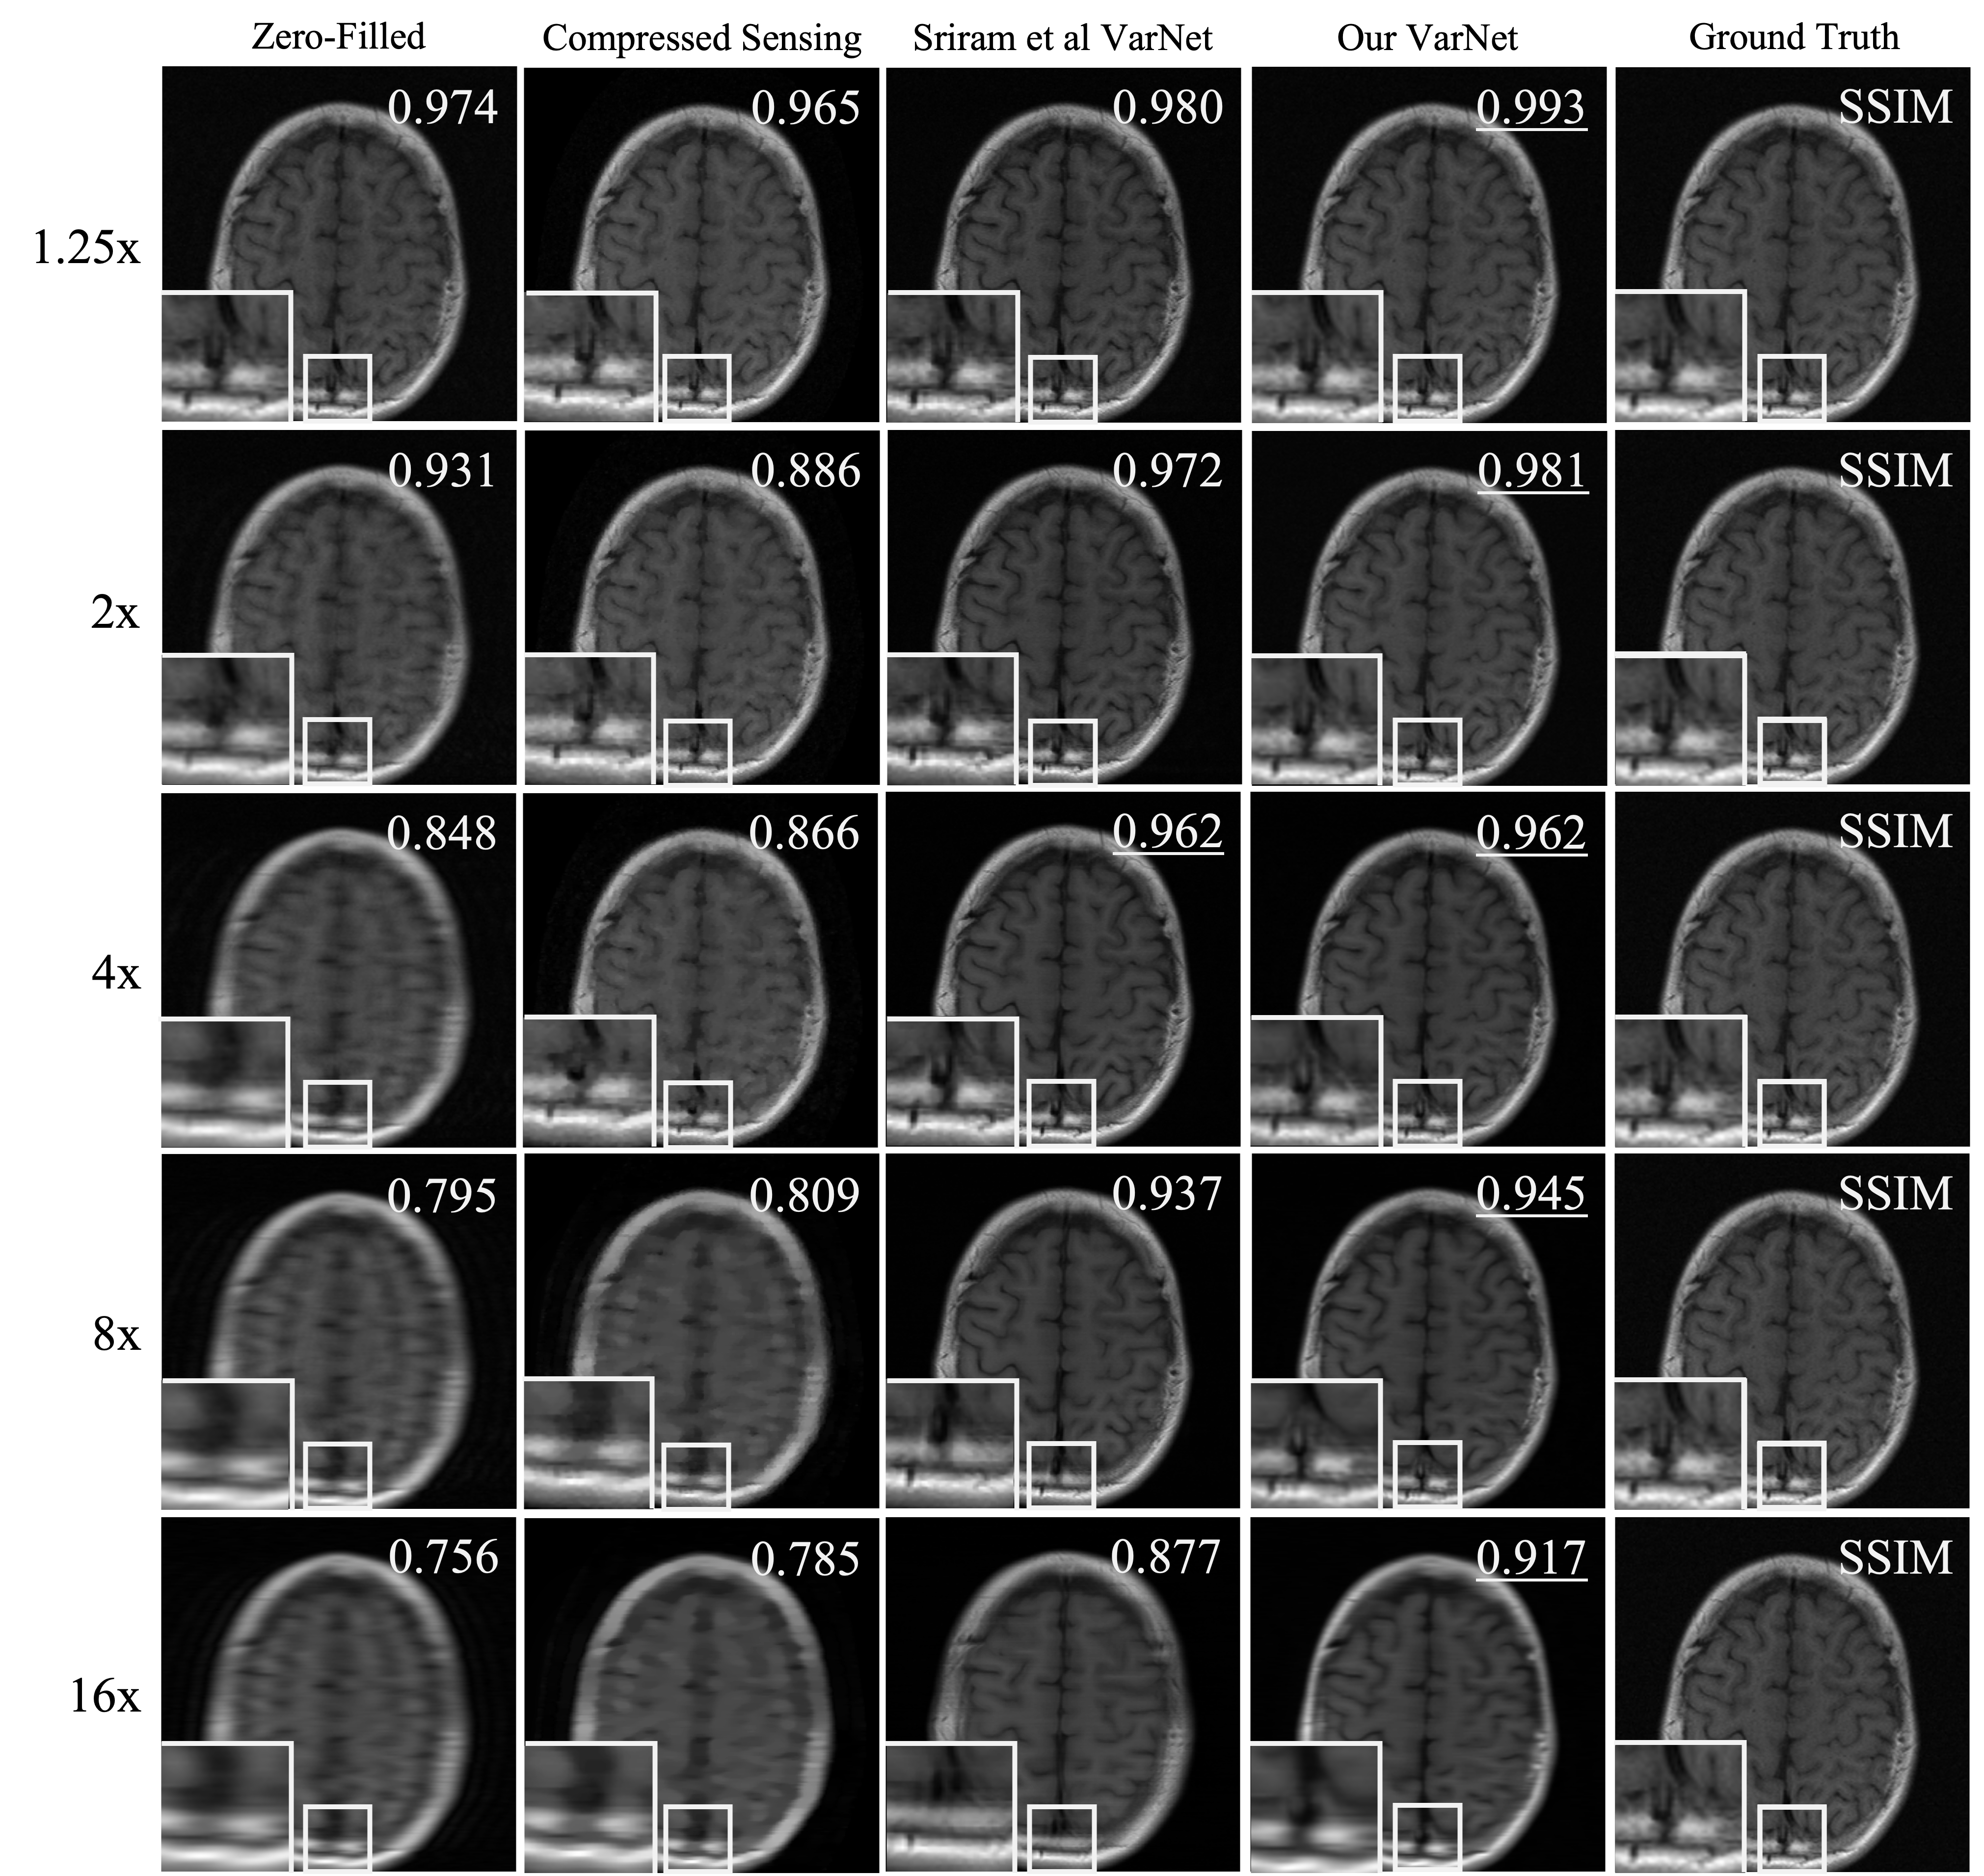

4.2 Acceleration Factor Balancing

Training our model on variably accelerated data improved its reconstructor performance on input data with acceleration factors that were either greater than 8x or less than 4x when compared to the original E2E-VarNet model (Sriram et al., 2020). However, we also noticed that our model performed comparable to Sriram et al’s original E2E-VarNet at 4x acceleration factor, and better than the original model at 8x acceleration factor (\tablereftable:reconstructor). This suggests that training accelerated MRI reconstruction models on variably accelerated data may offer improved performance at almost all stages of a clinical patient scan.

A.2 Acceleration Factor Balancing

To simulate variable acceleration factors, we randomly masked the slices in the fastMRI training by sampling the number of unmasked lines from a uniform distribution , where and width is the number of Cartesian -space columns in the slice. The acceleration factor could then vary anywhere between approximately 20x to a fully sampled dataset. Because the acceleration factor is proportional to the inverse of the fraction of unmasked lines, the distribution of acceleration factors in our training dataset therefore followed an inverse power law. Training was conducted on the fastMRI multi-coil knee training dataset partition. The results reported in \tablereftable:reconstructor were generated from the fastMRI multi-coil knee validation dataset, which was withheld during training of our model.

B.2 Acceleration Factor Balancing

In \tablereftable:reconstructor-brain-supp, we report reconstructor results exploring the impact of training reconstructor models on variably accelerated undersampled brain datasets. We also provide sample image reconstruction panels from our experiments in \sectionrefsection:var-acceleration to illustrate conclusions drawn from our experiments. Images were reconstructed using knee (\figurereffig:reconstructor-knee) or brain (\figurereffig:reconstructor-brain) models that were both trained on variably accelerated data. Finally, we include a panel of histograms in \figurereffig:var-knee-histogram visualizing the distribution of pair-wise SSIM improvement in undersampled multi-coil knee reconstruction using a reconstructor trained on variably accelerated data when compared to one trained on only 4x and 8x accelerated data.